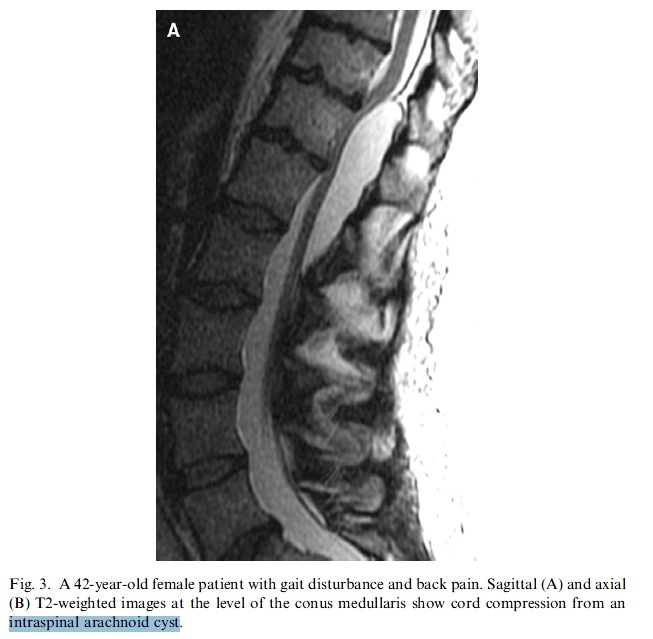

The most serious of symptoms related to thoracic disc herniation and radiculopathy is the development of myelopathy. As in the cervical spine, thoracic myelopathy can result in irreversible neurologic dysfunction and threaten spinal cord tracts. It is often the result of spinal cord compression of a large central thoracic disc, a calcified thoracic HNP, or an intradural herniation [13,21]. Bladder dysfunction, a wide-based ataxic pattern of gait, and upper motor neuron signs such as positive Babinski sign, ankle clonus, and hyperreflexia should be sought for in a patient with suspected myelopathy.

Mild lower extremity paraparesis is the most common symptom associated with thoracic disc herniation with myelopathy [22].